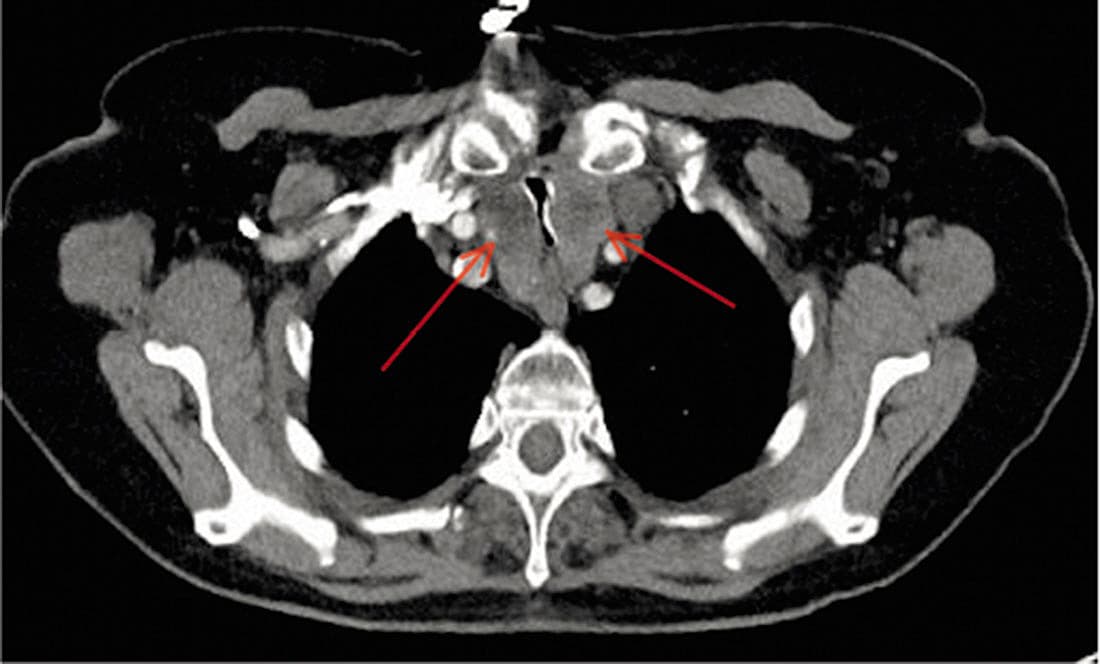

På grund af en let eleveret D-dimer blev der foretaget CT af thorax. Ved undersøgelsen påvistes ikke lungeemboli, men intratorakalt beliggende struma (markeret med røde pile) med udtalt kompression af trachea. Patienten gennemgik subakut total tyroidektomi, og hun fik hurtigt bedring i vejrtrækningen. I patologisvaret blev der beskrevet en nodøs kolloid struma.